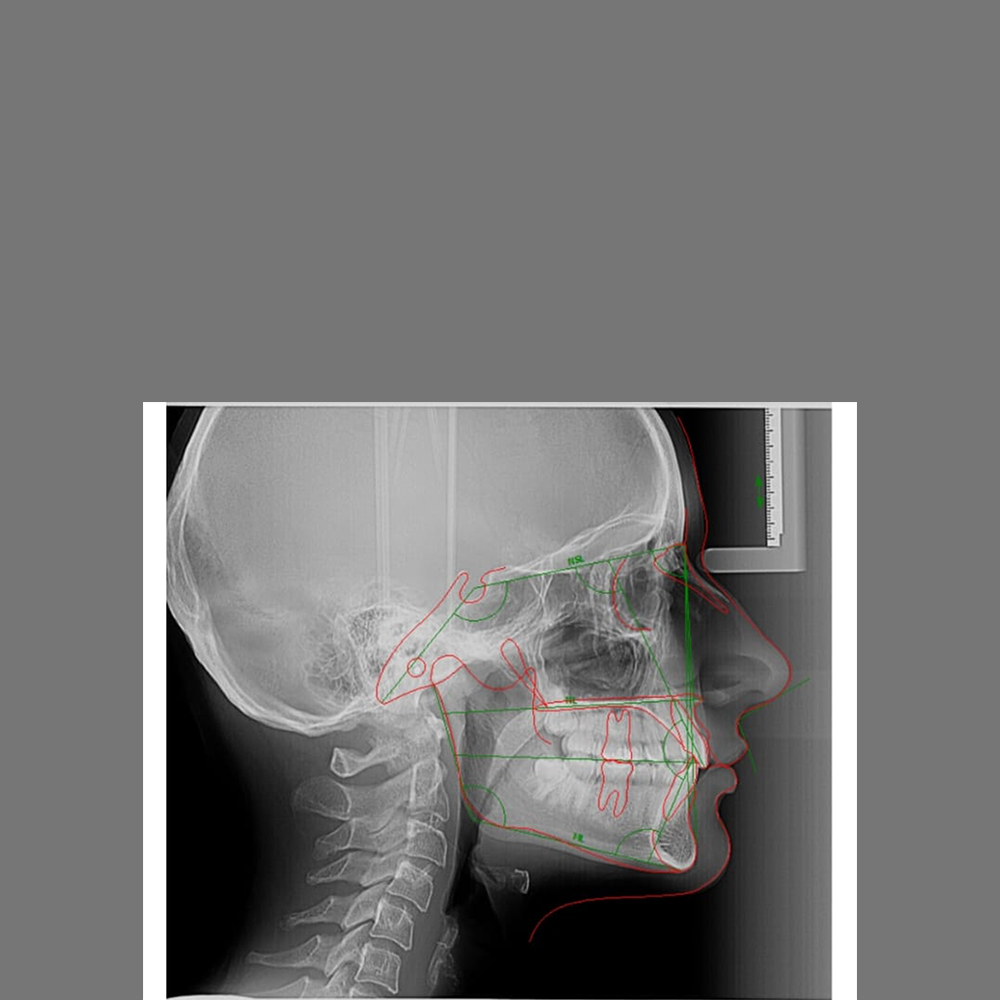

Craniu Lateral (CEPH)

Teleradiografia de craniu laterală (CEPH) este o investigație specializată utilizată în principal în ortodonție pentru analiza de profil.

110 RON

Analiză Cefalometrică

Analiza cefalometrică este procesul de măsurare și interpretare a teleradiografiei de profil, realizat digital pentru o precizie maximă.

200 RON